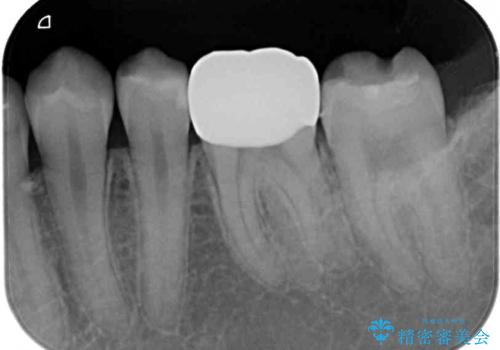

- 今まで色々と修復を重ね、いよいよものが挟まるとのことで来院された患者様です。

ものが挟まるだけであれば、インレーによる修復治療を選択しますが、今までの治療後が黒く汚く見えるとのことで、オールセラミッククラウンにて補綴治療を行うこととしました。

オールセラミッククラウンとしたことで見た目の改善やものが挟まる不快感の改善だけでなく、舌触りも良くなりました。